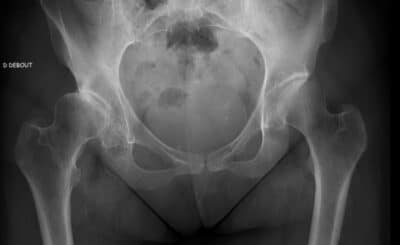

La coxarthrose , ou arthrose de la hanche, est l’une des pathologies articulaires les plus fréquentes. Elle se caractéri...